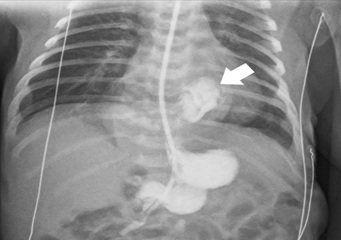

Upon admission to the pediatric intensive care unit, thoracoabdominal radiography (figure 3) and abdominal ultrasound demonstrated a partially intra-thoracic stomach, suggesting of a hiatal hernia with preserved diaphragm continuity. Echocardiogram revealed aortic isthmus narrowing with a maximum systolic gradient of 12 mmHg. The neonate was under continuous cardiorespiratory monitoring, and blood pressure, diuresis, and temperature were evaluated every four hours. He was breathing spontaneously with no signs of respiratory distress and had a nasogastric tube in passive drainage.

Figure 3: Thoracic and abdominal radiography on day 1 showing herniated intrathoracic stomach (arrow).

For preoperative evaluation, imaging was repeated on day two of life. Abdominal ultrasound and upper gastrointestinal series (figure 4) revealed the stomach now in anatomic position, intra-abdominal, with regular gastric emptying and significant gastro-oesophageal reflux. Diaphragmatic ultrasound disclosed a reduced thickness of the left hemidiaphragm and a reduced diaphragmatic excursion on this side (figure 5). Given these results, enteral feeding was started on day three and was initially well tolerated.

Figure 4: Upper gastrointestinal series on day 2 with an intra-abdominal stomach and significant gastroesophageal reflux (arrow).